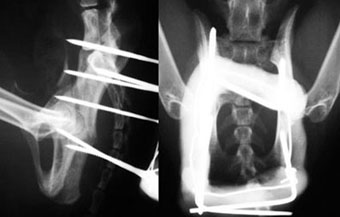

体重3kg、1歳齢の犬。

腸骨骨折と腹壁ヘルニアを起こしていました。

骨折部をプレート法により整復固定した後、腹壁ヘルニアの整復手術を実施しました。

写真上段: 手術前

骨盤の一部が割れて内側に変位しています。

写真下段: 手術後